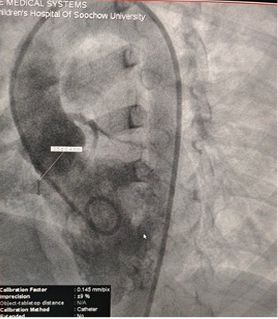

Successful Closure of Multi-Exit Membranous Septal Aneurysm-Type VSD Using MemoSorb Fully Biodegradable Occluder

Preoperative Echo Findings:

Base diameter: ~6.1 mm with multiple exit points

Membrane-like tissue observed over the defect

Color Doppler: Left-to-right shunt flow

Diagnosis: Perimembranous VSD

Challenge: Multiple exits + fragile membrane tissue

Selected MemoSorb ABFDQ-II 9 occluder based on intraoperative angiography and echocardiographic assessment.